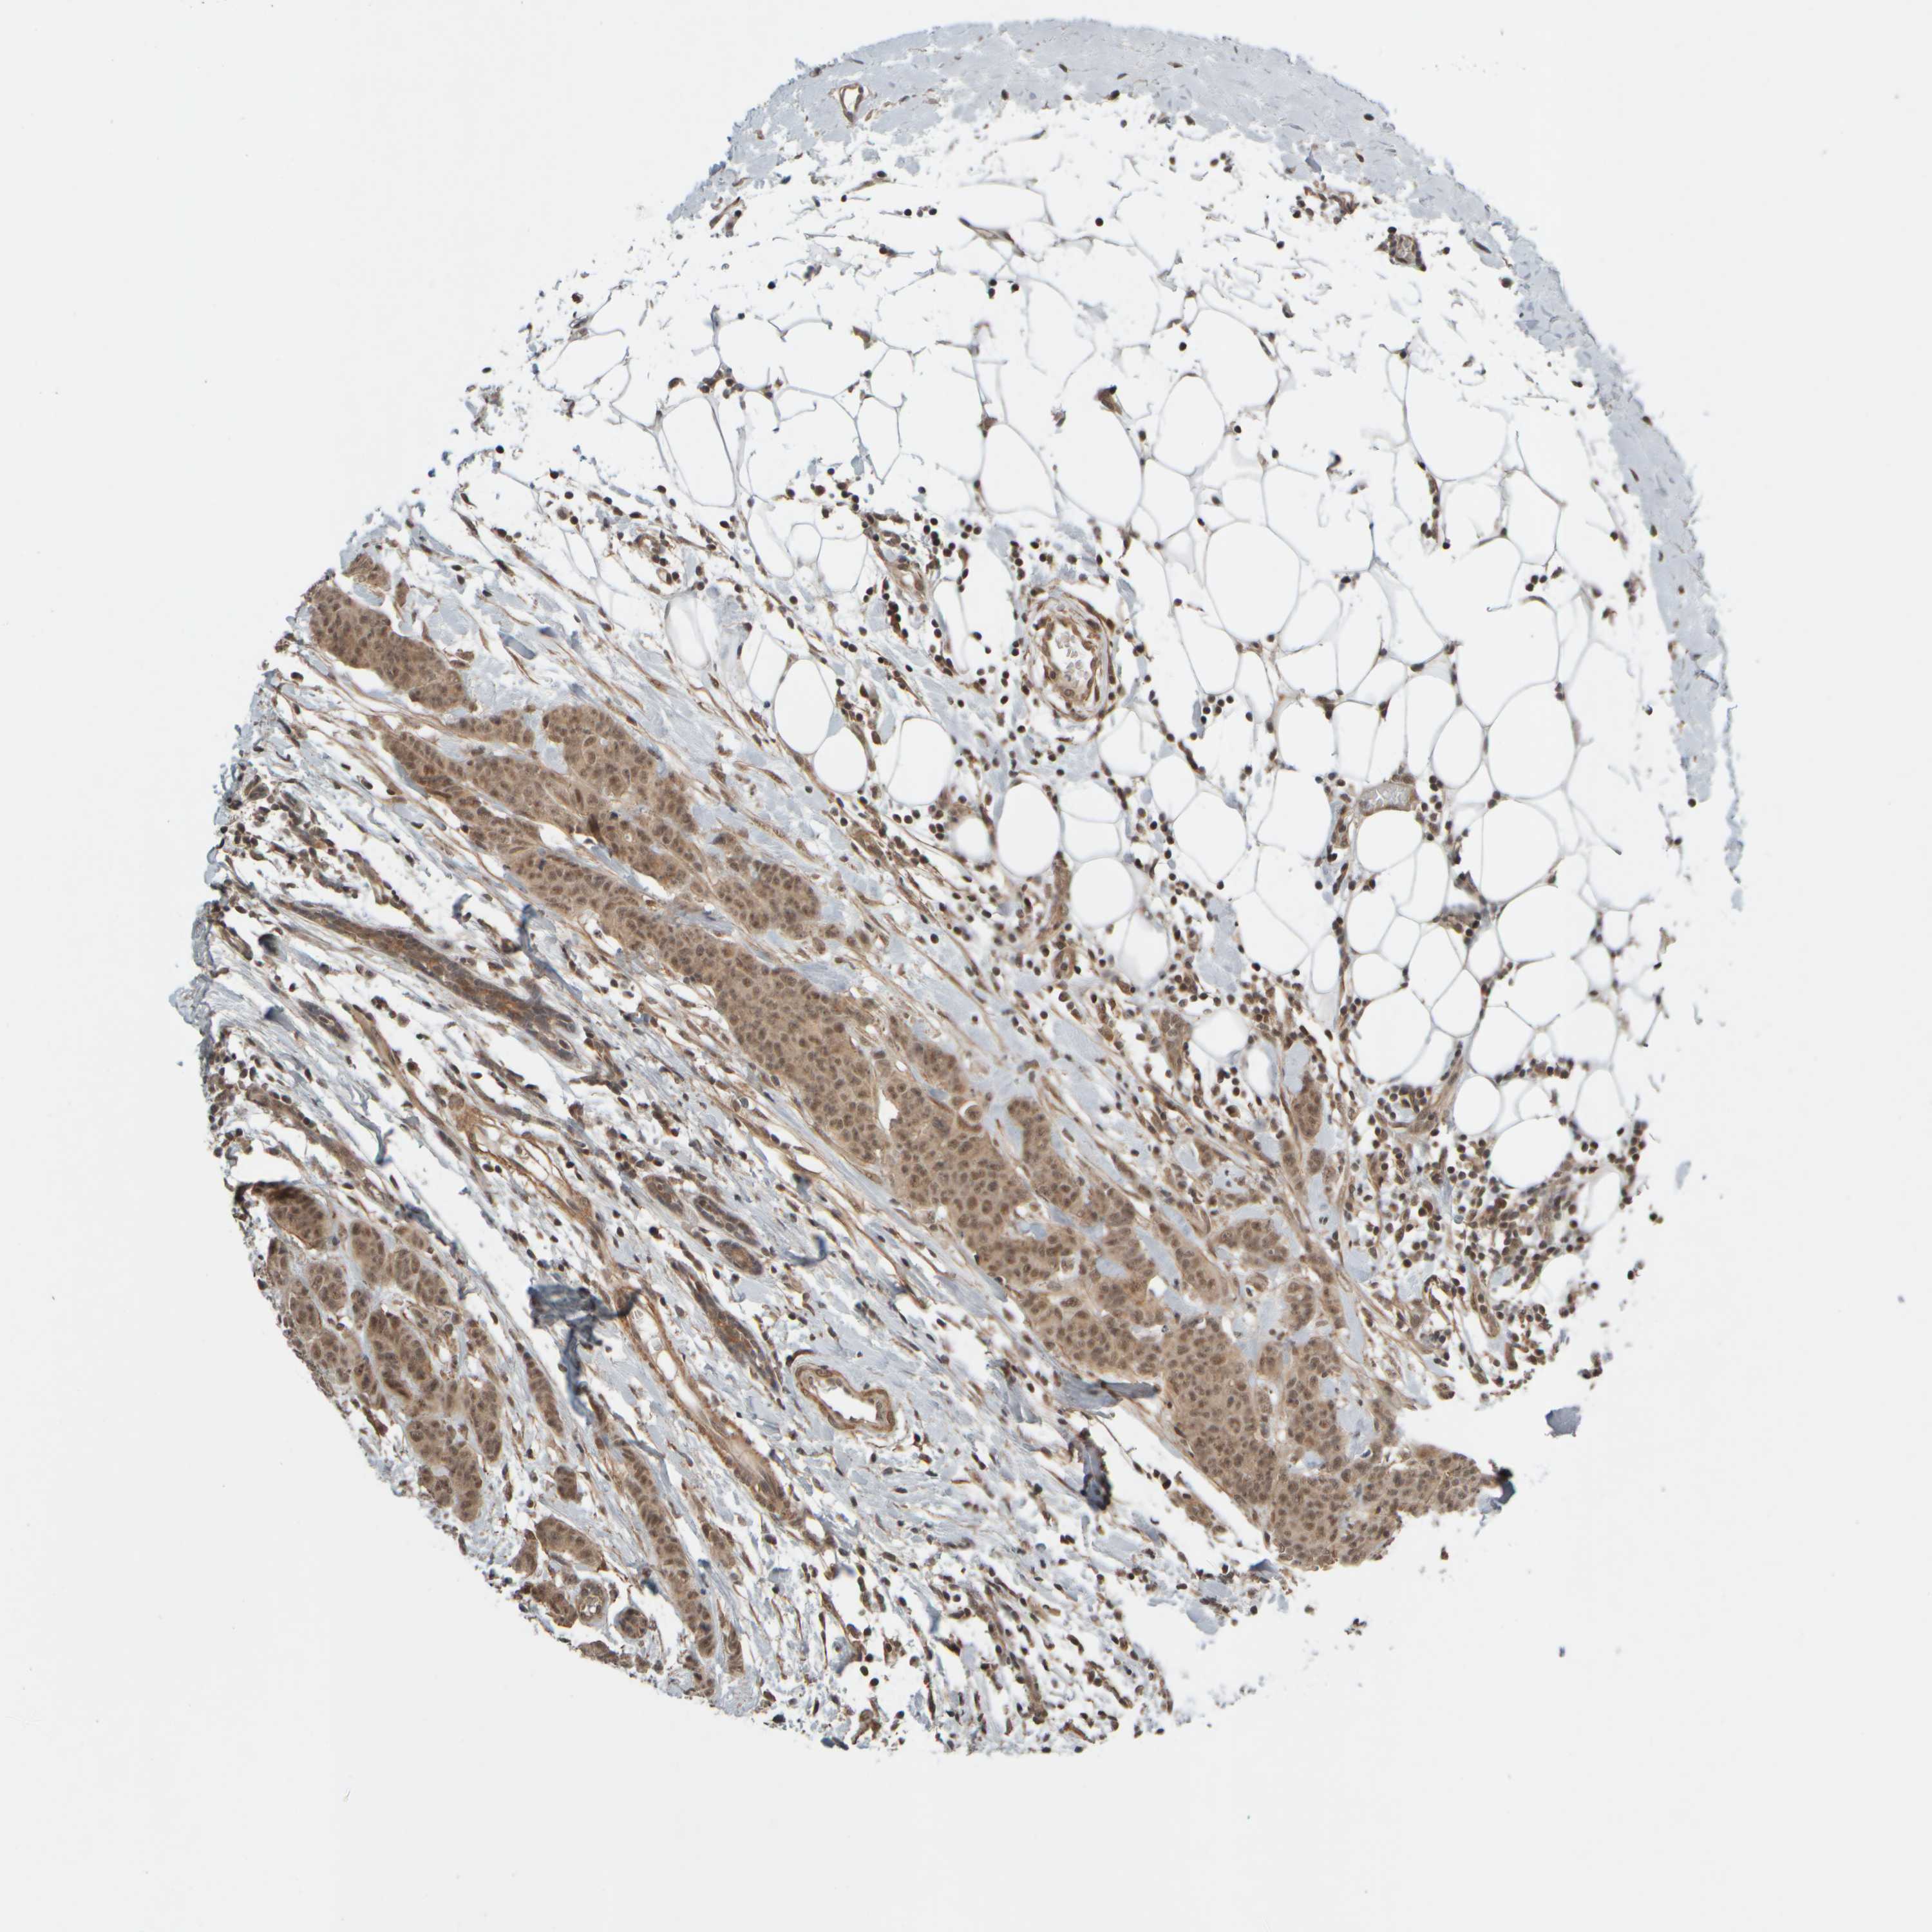

CANCER BREAST CANCER Show tissue menu

BRCA TCGA BRCA VALIDATION PROTEIN EXPRESSION